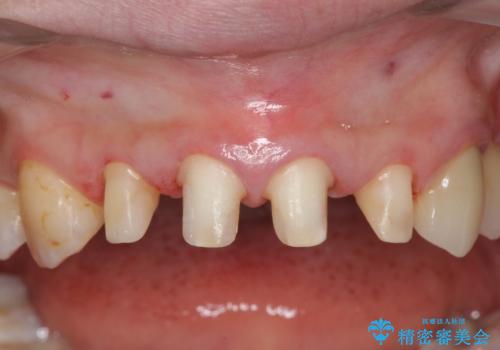

- 治療計画

- 矯正治療後に、前歯の樹脂の詰め物のやりかえを提案していましたが、治療は当時行いませんでした。

その後3年間来院がなく、その間に前歯の虫歯の進行があり、治療を行いました。

下の前歯との距離(クリアランス)が大きくは取れなかったため、ジルコニアクラウンではなくe-maxクラウンにしました。